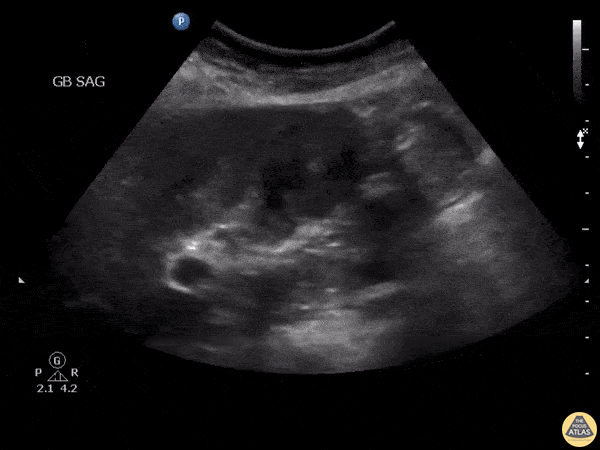

Patient presented with right upper quadrant pain. Clip shown demonstrated what appeared to be sludge however it was non-mobile and color doppler demonstrated internal flow. Further work up revealed gallbladder malignancy. Image courtesy of Robert Jones DO, FACEP @RJonesSonoEM Director, Emergency Ultrasound; MetroHealth Medical Center; Professor, Case Western Reserve Medical School, Cleveland, OH View his original post here